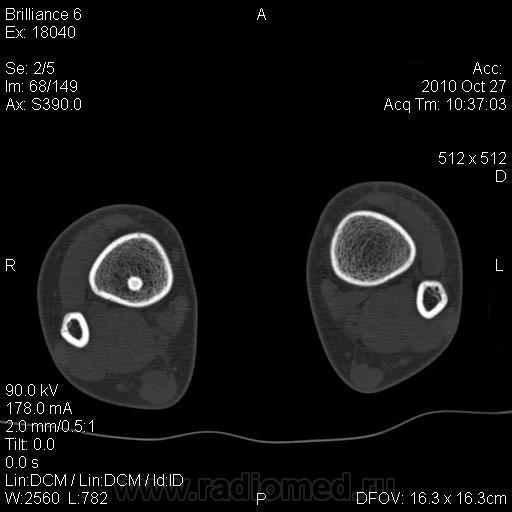

Мальчик 10 лет. Обратился за помощью по поводу травмы голеностопного сустава. До травмы ничего не беспокоило. При рентгенобследовании выявлена следующая картина. Мы думаем об эностозе. Хотелось бы знать мнения уважаемых коллег.

Какой то эностоз "не эностозный"...

Я не КТ-эшник, но не похоже это на участок некроза костного мозга?

Такое впечатление, что внутри этого образования есть костный мозг..

Я тоже за патологию костного мозга, раз больше ничего нельзя предложить, но даже для этой патологии, картинка очень странная.

Выглядит как кость в кости. Может, это врожденная фигня, подобная тератоме? Этакая недоделанная косточка с недоделанным костным мозгом в костномозговой полости большеберцовой кости?

ИМХО: это не похоже, на инфаркт костного мозга. Скорее, это всё же эностоз ( раньше ни когда не видел этого на КТ и жаль, что не представлены, более привычные рентгенограммы )  но, я хотел бы знать мнение Татьяны Павленко!

Обычные рентгенограммы просто отвратительного качестваsad. Но выглядит все, как и на обзорной КТ (первый снимок) - линейный участок повышенной плотности с четкими контурами.